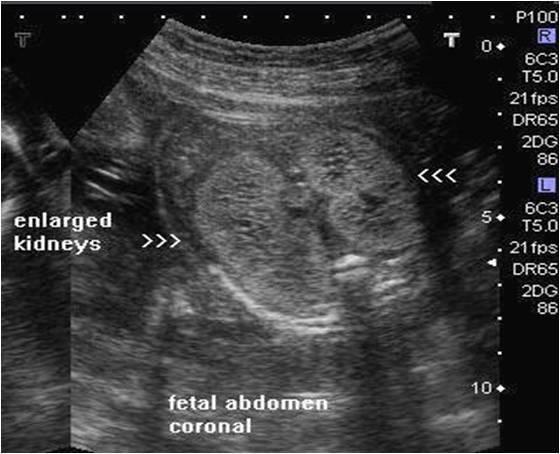

What is IPKD?

disorder associated with multiple bilateral cysts

Infantile Polycystic Kidney Disease

Infantile Polycystic Kidney Disease

What is another name for IPKD?

Potter Type 1

Is IPKD recessive of dominant?

recessive

What are the 4 groups of IPKD?

Perinatal – renal failure in utero

Neonatal

Infantile

juvenile

What is the sonographic appearance of IPKD?

enlarged

hyperechoic

homogeneous hyoerechoic large kidneys

increased kidney AC

small bladder

loss of corticomedullary differentiation